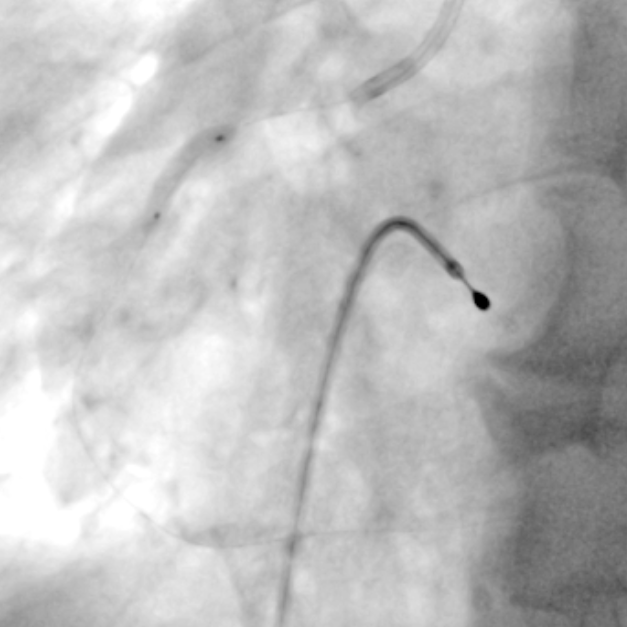

冠脉造影

PCI过程-球囊PTCA

预置临时起搏器后,7F AL1.0无法到位,更换为7F SAL1.0至RCA开口,应用非顺应性球囊2.5X15mm,于RCA中段病变处以12-18atm扩张,球囊膨胀不佳。